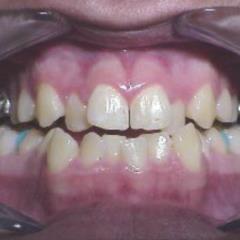

- We are discussing expansion. I am sure, we all have done few. We will revisit protocol.

- There are also other types of expanders besides RPE and we will look intot hem as well.

- Narrow maxilla is indicative of expansion in presense of a crossbite however, expansion is being used as a corrective treatment in Class II and Class III cases as well. We will examine latest literature on the subject.